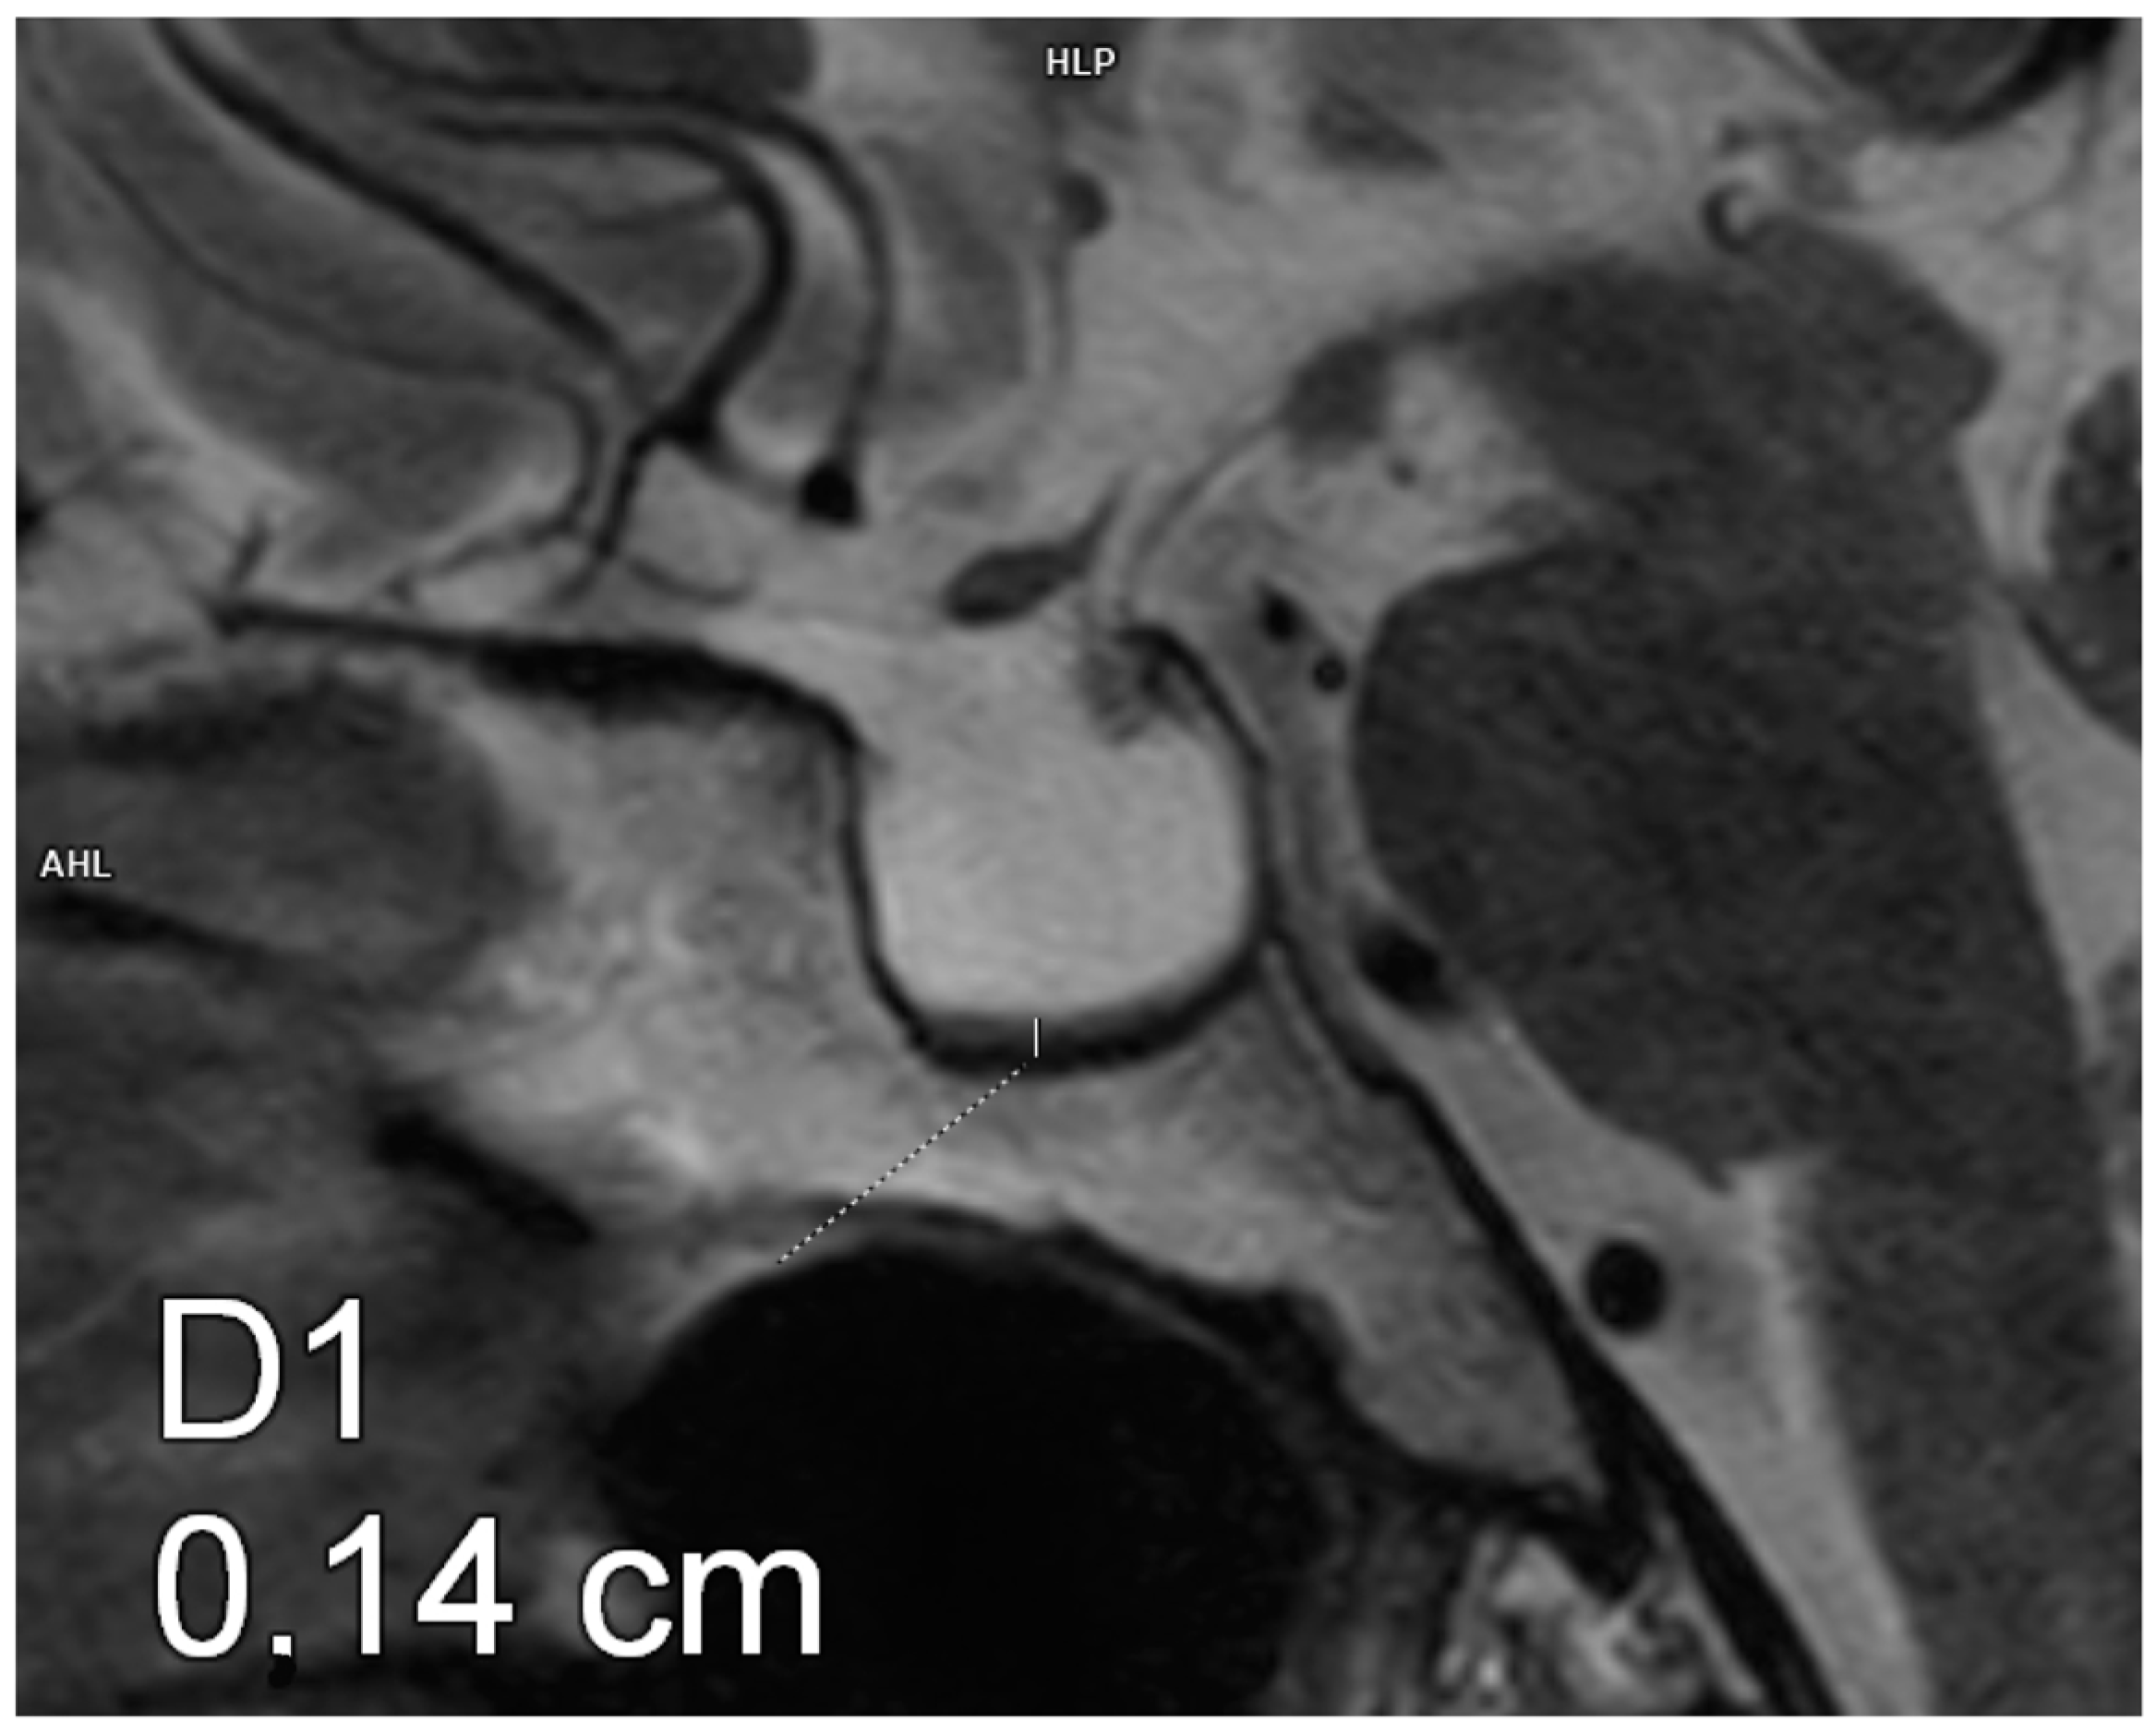

Figure 2.

Partial empty sella. Magnetic resonance imaging, T2-weighted image, sagittal plane. The craniocaudal diameter of the pituitary gland is 3.5 mm.